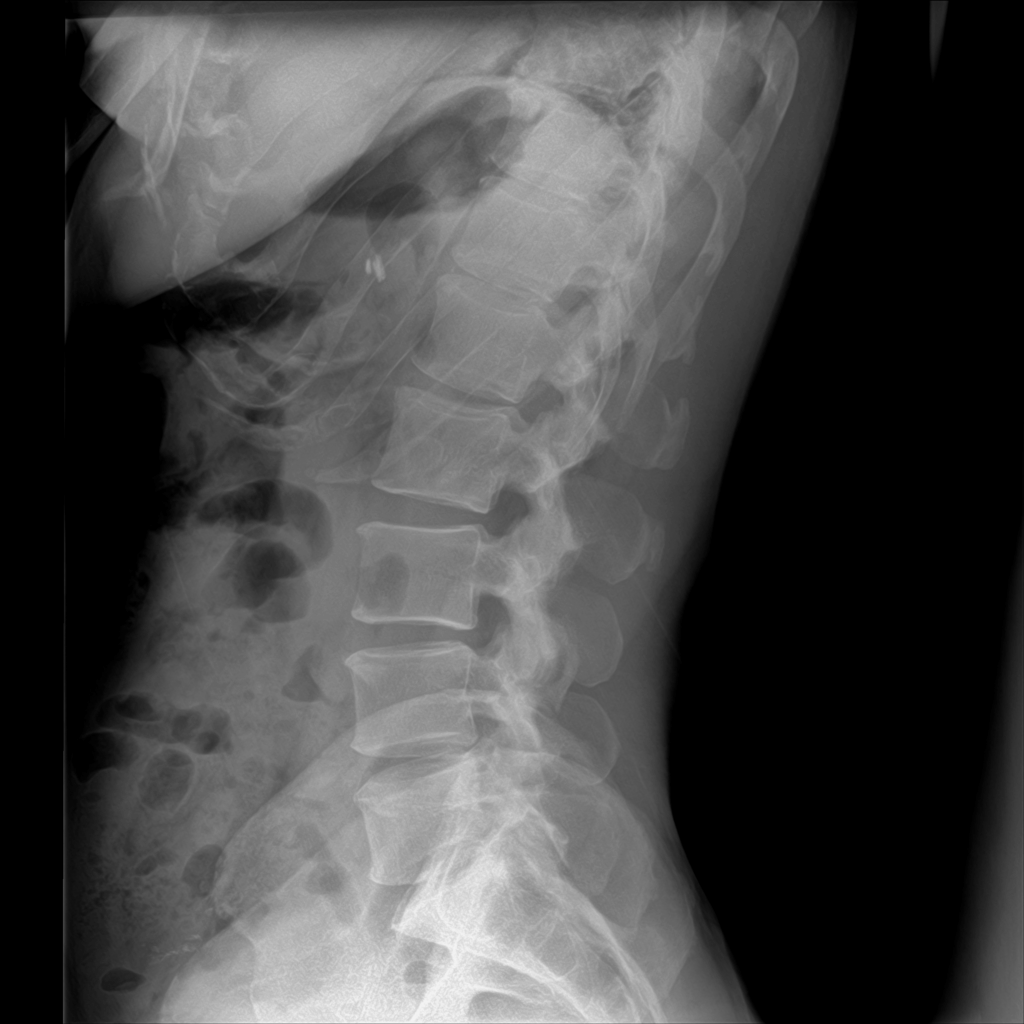

Degenerative Disc Disease (DDD), also commonly referred to as degenerative joint disease, is one of the most widespread spinal conditions affecting millions of Americans today. It can lead to disc bulges, herniations, or ruptures. Despite these similar-sounding names, they all point to the same underlying issue: the gradual breakdown of the cushioning discs between your vertebrae.

The numbers surrounding DDD are eye-opening. Research shows that by age 20, approximately 37% of people already show signs of disc degeneration on imaging studies–and believe me, I see this almost every day in my office. This percentage dramatically increases with age – by 50 years old, about 80% of people have some degree of disc degeneration. For those over 40, approximately 40% have at least one degenerated vertebral disc, and this number jumps to 80% by age 80.

According to recent Medicare data analysis, the overall prevalence of spine degeneration has increased from 24.2% in 2005 to 30.1% in 2017, highlighting this growing health concern. The Wakayama Spine Study found that more than 90% of both men and women over 50 years old show signs of disc degeneration.